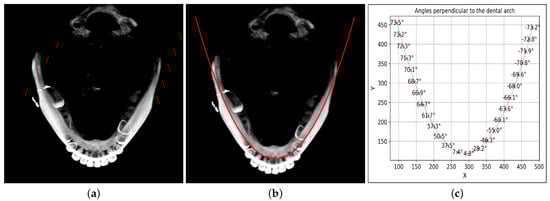

- Dental Arch Approximation and Extension: The proposed framework employs the quadratic kernel-based curve fitting to generate a mathematical expression that best fits the dental arch. The extension of the dental arch up to the TMJ locations is then obtained through that quadratic expression.

- Localized Maximum Intensity Project Stitching: Trajectory-based cubic segments are extracted and rotated to an angle perpendicular to the dental arch at that specific coordinate point. The localized MIP obtained from each rotated cubic segment is then cropped and stitched together to obtain the panoramic view of the given CBCT data.